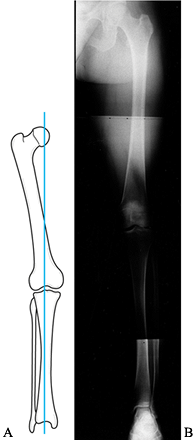

is useful for assessing the mechanical axis of the limb. The mechanical

axis normally falls through the medial tibial spine (Fig. 84.16).

Shift of the weight-bearing axis into either compartment leads to

relationship of the collateral ligaments (Fig. 84.17). This view is essential for preoperative planning in patients undergoing total knee replacement,

osteotomy, ligament reconstruction, meniscus reconstruction with an

allograft, or chondrocyte autograft. Without proper attention to the

mechanical axis before surgery, the outcome of these procedures may be

compromised.

Figure 84.16.

The mechanical axis measured on a 51-inch weight-bearing AP is sensitive to demonstrating shift of the weight-bearing axis into the medial or lateral compartment. |

Figure 84.17. Fifty-one-inch standing AP weight-bearing view demonstrating shift of the weight-bearing axis into the medial compartment.